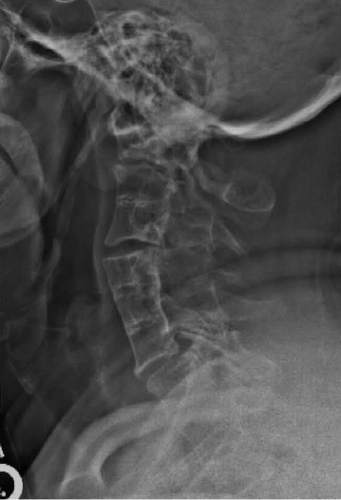

A 51-year-old male presented to us with numerous craniocervical developmental abnormalities and severe cervical myelopathy because of occipitocervical assimilation, basilar invagination, and C1-2 instability. He was admitted for preoperative cervical traction, which provided partial reduction of the basilar invagination (Figures 8-1 and 8-2).